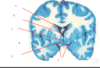

which of the following is the lateral ventricle?

A

B

C

D

E

which of the following is the lateral ventricle?

A

B

C

D

E